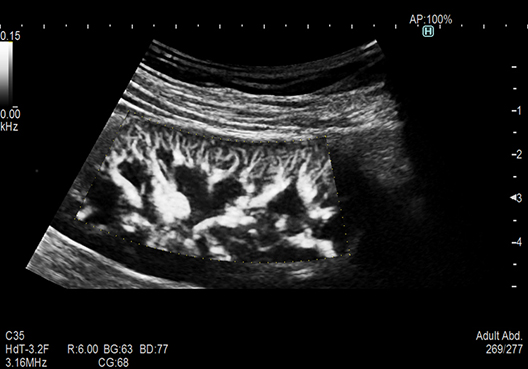

RTE assesses tissue strain in real time and displays the tissue stiffness as a color map. Its application has been validated in a wide variety of clinical fields, and it is possible to calculate an estimate value of liver fibrosis staging.